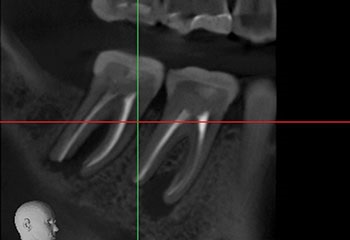

Fig. 26: Preop CBCT SAG.

Endodontic Root Fracture Case Series

Fig. 27: Preop CBCT AX

Fig. 28: Postop CBCT SAG.

Fig. 29: Postop CBCT AX.

A patient solicited a second opinion after her dentist recommended extraction of #18 because of a suspected VRF, apparently suggested by a midbuccal probing defect.

This tooth had irreversible pulpitis, and RCT was initiated. Examination of the pulp chamber using a microscope did not reveal any cracking. A lateral canal leading to the furcation was identified but could not be negotiated. Hence, this tooth was treated in three visits using a calcium hydroxide intracanal medicament and obturated after resolution of the pocket and bony healing were confirmed.